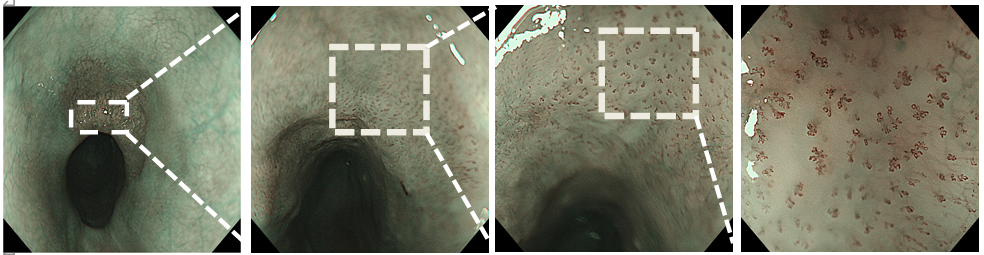

复原图如下:我们进一步行放大内镜下病理复原图的对应,1号标本IPCL稀疏,呈拉长、扩张及扭曲,为不典型B1改变,可见肿瘤细胞仅仅局限于基底膜周围,范围不超过上皮层下1/2,其上方可见正常鳞状上皮细胞覆盖。

6号标本IPCL呈典型B1改变的区域,肿瘤细胞已经突破基底膜,向固有层浸润,局部表面可见正常的鳞状上皮。

14号标本典型IPCL的区域,肿瘤细胞已经完全累及整个上皮层全层。